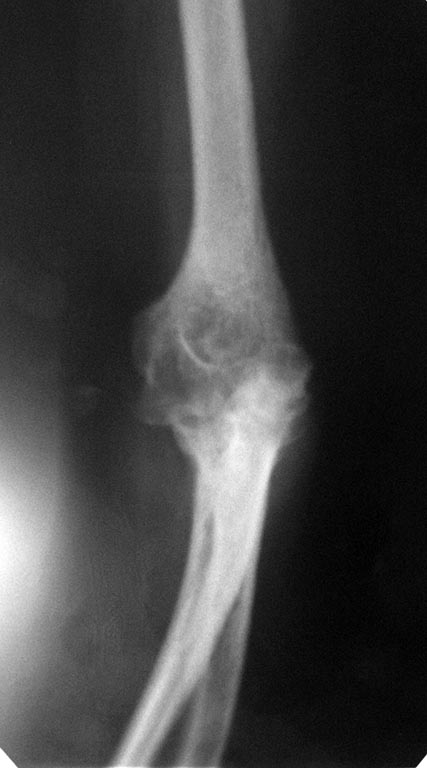

У женщины 54 лет имеются последствия закрытого вывиха костей предплечья...

Травма 08.11.14 г., окончательное вправление лишь 10.11.14 г., тогда же появились признаки нейропатии локтевого нерва, они остаются до сих пор.Движения в суставе качательные, практически анкилоз в положении 90 град.

Снимки КТ в приложении.